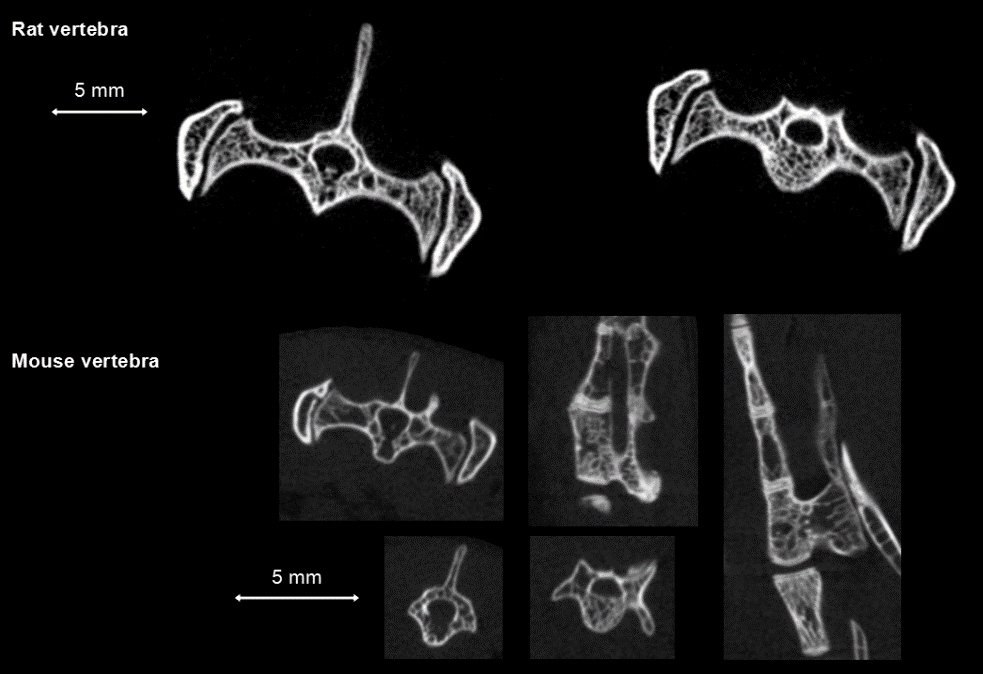

1、骨骼:由于骨骼與其它身體組織在X射線衰減性能方面有相對明顯差別,因此骨骼研究是臨床前CT最主要的應用之一??蛇M行皮質骨與骨小梁分析,其變化與骨質疏松、骨折、骨關節(jié)炎、局部缺血和遺傳疾病等病癥有關,也可以研究骨骼腫瘤。

(2)骨骼研究:研究不同基因或信號通路對骨骼的數(shù)量或質量的影響、疾病狀態(tài)對骨骼發(fā)育/修復的影響、細胞因子對骨折后組織修復時血管生長的影響,等。

鼠的脊椎骨活體測量:高清晰度環(huán)形獲取,獲取時間:4min,F(xiàn)DK重建,50和20μm voxel size。

脊椎骨測量.png